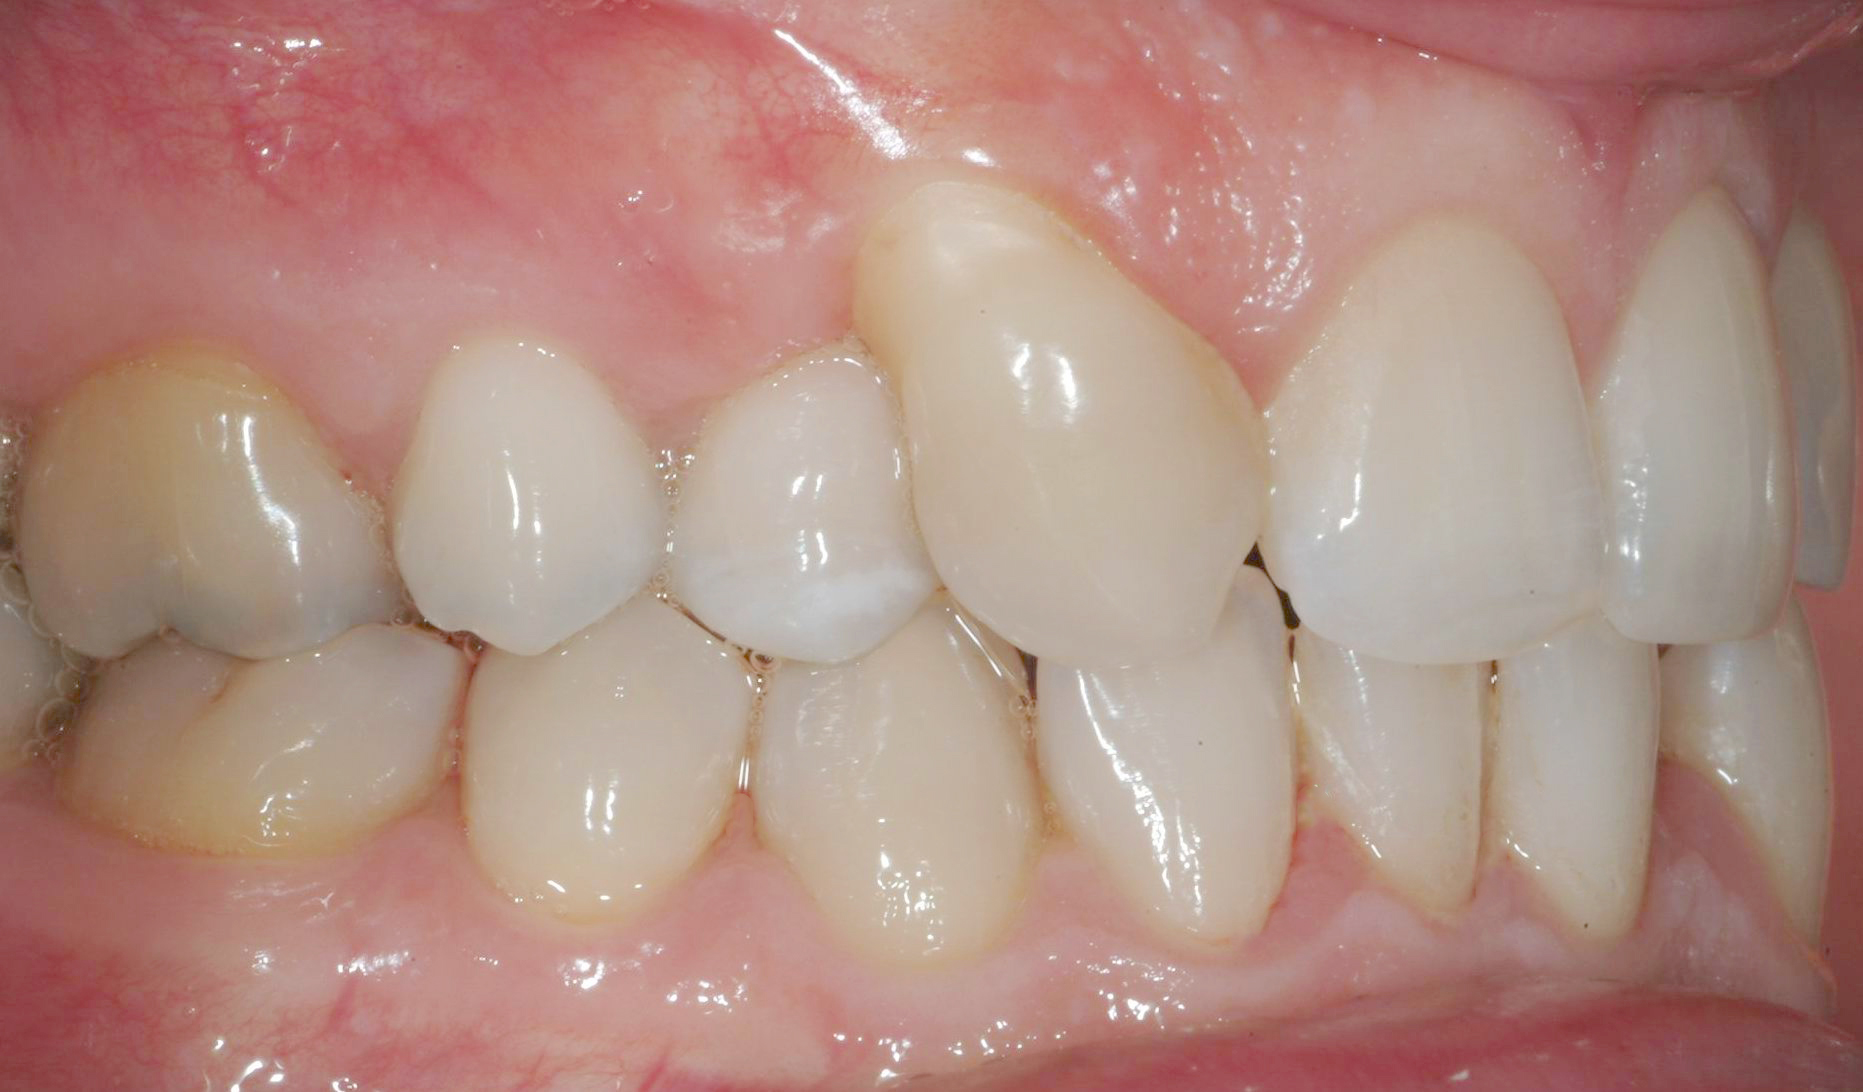

Una paziente di sesso femminile, 38 anni, già trattata ortodonticamente presso altra sede con apparecchiatura fissa a entrambe le arcate in età adolescenziale senza successiva applicazione di alcuna contenzione, si presenta alla nostra attenzione perché insoddisfatta dell’estetica del sorriso; richiede una valutazione per un trattamento ortodontico con apparecchiatura fissa linguale per la presenza di affollamento dentale a entrambe le arcate e difficoltà a mantenere una adeguata igiene orale; si riscontrano agenesia di entrambi gli incisivi laterali superiori (1.2 e 2.2) e del secondo premolare inferiore destro (4.5). Presentiamo la risoluzione del caso mediante trattamento ortodontico estrattivo a entrambe le arcate, eseguito con apparecchiatura linguale invisibile 2D e meccanica asimmetrica e seguito a medio termine da riabilitazione implanto-protesica e contenzione fissa.

Per formulare corretta diagnosi e piano di cura, lo studio del caso ha previsto la raccolta di documentazione completa standard, ovvero fotografie del viso e intraorali (Figure 1a-e), radiografia panoramica e teleradiografia del cranio in proiezione laterale (Figure 2a-b) per la relativa analisi cefalometrica e modelli di studio.

La valutazione clinica e gli esami effettuati confermano la presenza di agenesia degli incisivi laterali superiori (1.2 e 2.2) e del secondo premolare inferiore destro (4.5).

L’analisi ortodontica e la valutazione parodontale, con particolare riferimento alla posizione della radice del canino superiore destro (1.3), distoinclinata e trasposta alla radice del primo premolare (1.4) come evidente dalla radiografia panoramica e dalle immagini intraorali, ci hanno guidati nella programmazione di un trattamento estrattivo asimmetrico a entrambe le arcate.